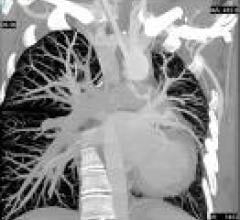

The clinical adoption of 64-slice CT equipment has spiked over the last two years due, in large part, to an…

It’s no secret many clinicians have predicted coronary CT angiography (CCTA) would replace invasive angiography for…